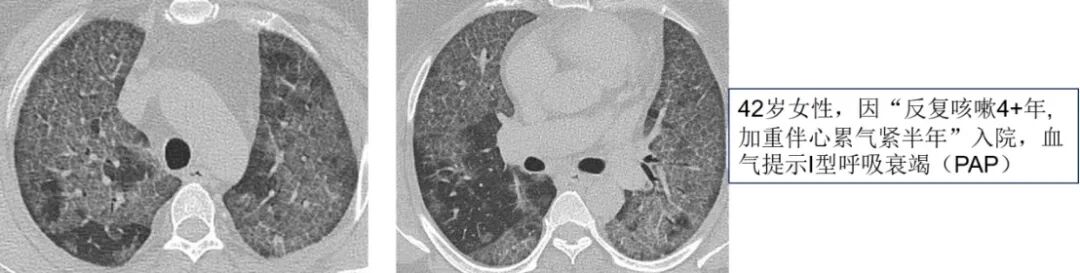

第三步,结合患者病史特征。虽然影像学特征能够提供鉴别方向,但单独影像学很难具体诊断某种疾病,因此需结合患者病史特征,包括详细的问诊及查体等。首先,我们需考虑疾病起病缓急,以双肺GGO为主要表现急性起病的疾病包括肺水肿、肺出血、PCP、支原体肺炎、病毒性肺炎、急性间质性肺炎、急性嗜酸性粒细胞肺病、早期过敏性肺炎、药物反应、淋巴瘤等;而慢性起病的疾病包括过敏性肺炎、DIP、RB-ILD、细胞性非特异性间质性肺炎、肺泡蛋白沉积症、细支气管肺泡癌(原位腺癌)、机化性肺炎、结节病。以下图病例为例,患者因重度Ⅰ型呼吸衰竭就诊,双肺表现为铺路石征及地图样改变,如果急性起病,我们可能首先会考虑PCP等可能,而患者4年缓慢进展的病史提示肺泡蛋白沉积症等慢性进展性疾病的可能性更大,而最终的肺泡灌洗液病理证实肺泡蛋白沉积症。